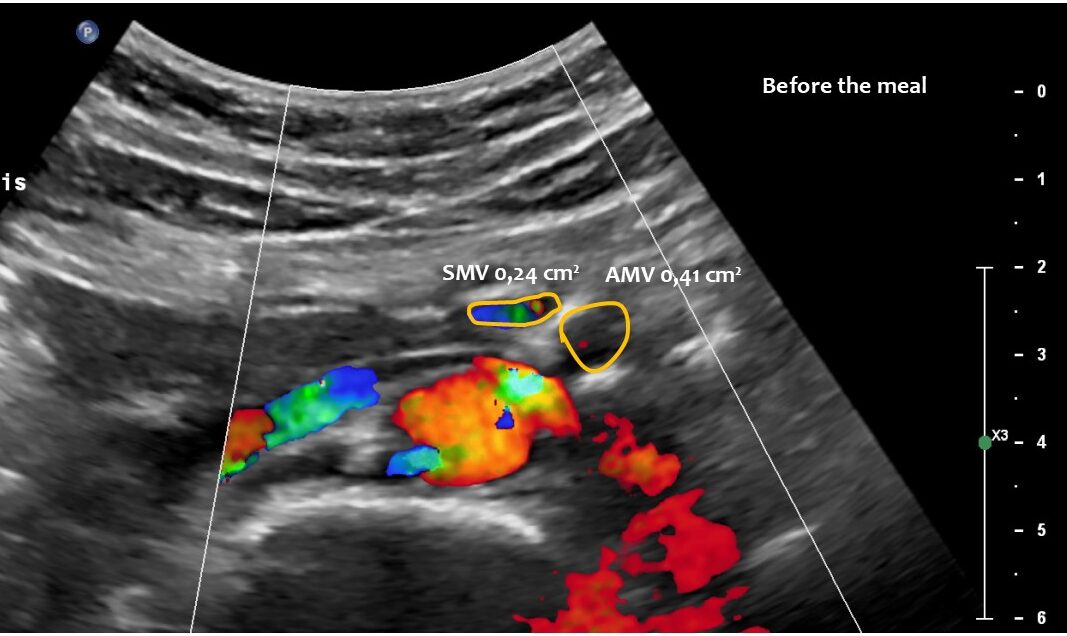

Normal size of the superior mesenteric vein which is slightly slimmer than the superior mesenteric artery as long as the patient was fasting. However, due to the limited space in the flat upper abdomen the superior mesenteric artery already is shifted to the left side of the aorta instead of lying precisely in front of it.

Here, the unique mechanism causing compression of the duodenum by the enlarged superior mesenteric vein is demonstrated. In contrast to conventional SMA syndrome, the superior mesenteric vein acts as a pillar against which the aorta presses, thus obstructing the duodenum. It is important to be aware of the variability in the position of the superior mesenteric artery in patients with a flat abdominal cavity. When the stomach is full, it may shift further to the left (or right) of the SMA than in the fasting position.

Enlargement of the superior mesenteric vein can be observed as early as five minutes after eating, progressing to fivefold enlargement of the transsectional area after seven minutes.